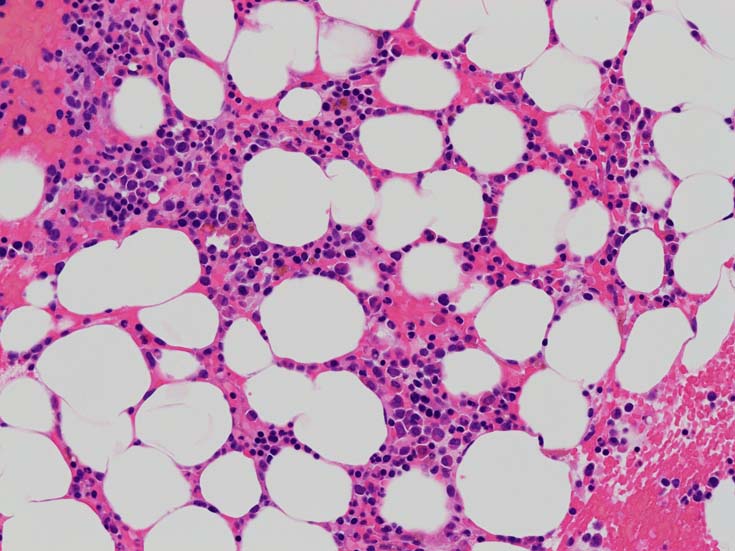

MDS症例のHbF発現.

サムネイル画像をクリックすると大きな画像が見られます.

MDSでの赤芽球HbF発現は, 陽性細胞はそれほど多くない印象ですが, この低形成性MDS症例では, 多くの陽性細胞がaggregatesを形成していました.